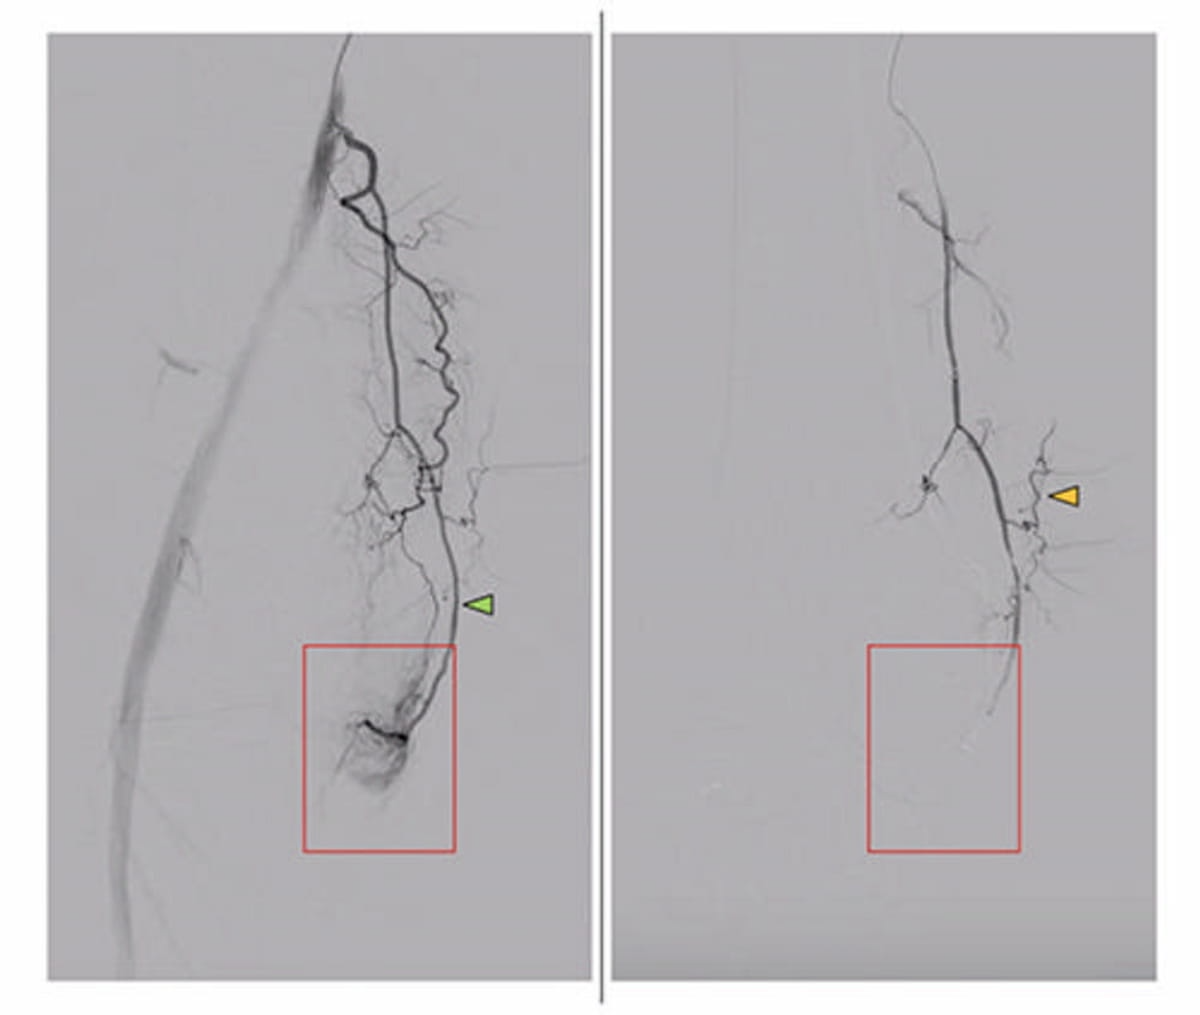

Здесь можно увидеть изображения, показывающие нисходящую коленную артерию у пациента с симптоматическим остеоартритом коленного сустава. Изображение до эмболизации (слева) показывает гиперемический румянец (красный прямоугольник), тогда как изображение после эмболизации показывает полное устранение гиперемического румянца. (Изображения предоставлены RSNA.)